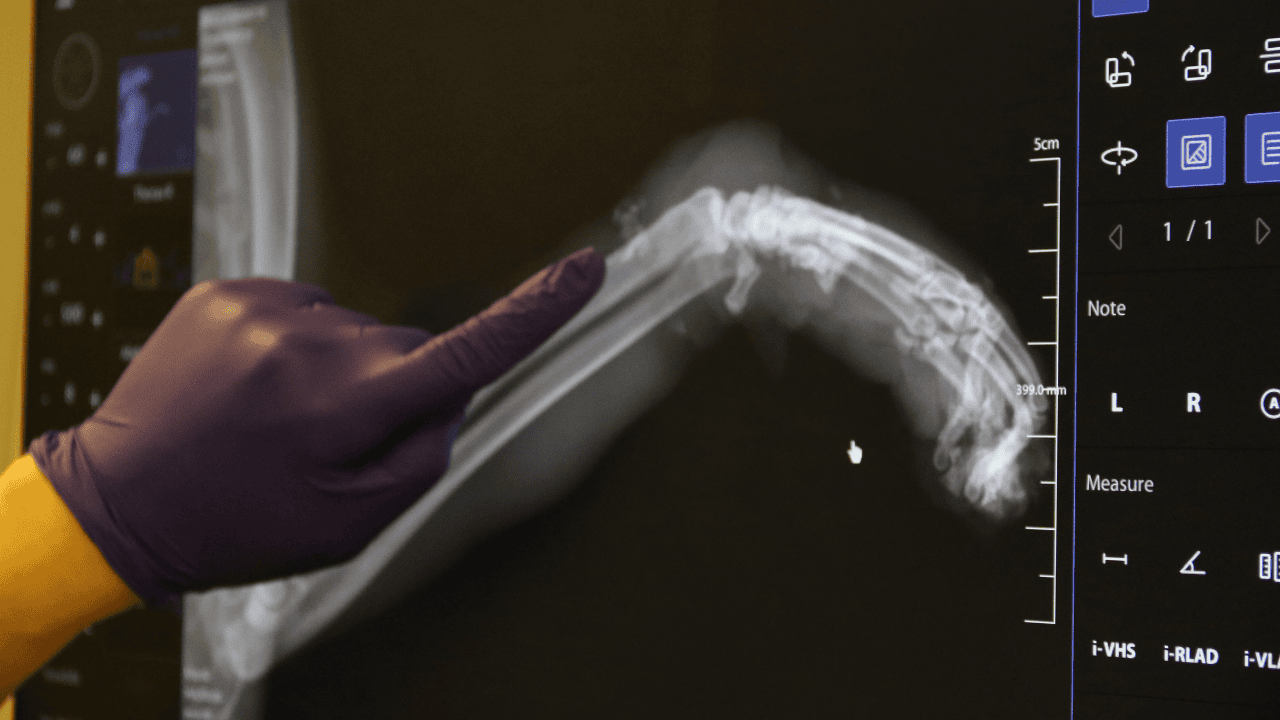

Veteriner hekimler, kedinin patisindeki paket lastiğini çıkararak tedaviye başladı. Kedinin sol ön ayağında ödem birikmesi nedeniyle, veterinerler ayağının röntgenini çekti. Yapılan tetkiklerde, ayağın kangren olma riski bulunduğu ve bu durumda ayağın ampute edilme ihtimalinin olduğu belirtildi. Kedinin tedavisi antibiyotiklerle devam ederken, gözlem altına alındığı öğrenildi.

Kedinin tedavi süreci hakkında bilgi veren Veteriner Hekim İlayda Ulus, "Kedi saat 4 gibi geldi kedimiz. Bacağı aşırı derecede şişmiş, ödenmiş şekilde geldi. Biz ilk başta kırık sandık. Ama muayene ettiğimizde 4-5 kere bağlanacak şekilde lastiğin burasını boğmuş olduğunu gördük. Bu bilinçli şekilde yapılmış. Dolaşım bozmak adına. Kimin yaptığını bilmiyoruz. Hasta sahibimiz getirdi çok üzülerek. Biz de tedaviye başladık şu anlık. Sokak kedisi, birisi sadece dükkanında bakıyormuş, gidip geliyormuş. Bir haftadır yokmuş kedisi. Aramışlar, birisi haber vermiş tasmasından bularak o şekilde geldi. Oradaki tüyleri özellikle tıraş ettik. Ölü dokuları aldık. Baya bir kan toplamış ve ölü dokular birikmiş. Onları temizledik, tıraş ettik. Antibiyotik tedavisine başladık. Şu anda sabah akşam olacak şekilde krem sürüyoruz. Yarın tedavisi yapıyoruz. Oradaki kan akımını hızlandıracak kremler, özellikle fizik tedaviler uyguluyoruz. Şu anda 3-4 gün takip edeceğiz. Eğer iyileşme görmezsek amputeye doğru gidebiliriz. Şu anda sol ön ayağını kaybetme ihtimali var. Birkaç kere böyle tasma boğulmuş şekilde geldi, boyundan yara almış kediler. Başka tekme çok geldi, göğüs kırıkları. Bu tür vakaları gördük. Onların ağzı var, dili yok. Bizden daha daha masumlar. Bu şekilde olması bizi çok üzüyor, derinden üzüyor. Hayvan sevmeyen, insan sevemez. Bu şekilde çok daha duyarlı ve dikkatli olmalarını bekliyoruz" dedi.